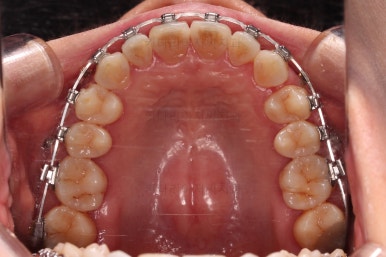

초진 시, 입안의 모습이에요.

이번에 사용하신 장치는 엠파워 메탈이라고 하는 자가결찰 금속 장치인데요.

금속 재료를 시각적으로 신경쓰지 않으셔꼬 메탈장치가 세라믹에 비해 양치라던지 잇몸에 그래도 약간의 장점이 있어서 추천되기도 했어요.

앞니 사이의 틈을 줄이고, 앞니를 뒤로 넣기 위해서는 어금니 -> 아래 앞니 -> 윗니 앞니 순서대로 문제가 해결되어야 합니다.

윗니 앞니가 제일 보기 싫더라도 가장 늦게 개선되는 부분인거죠.